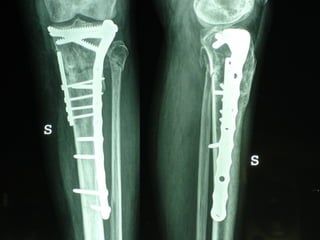

Dal Gennaio 2000 al Febbraio 2006 abbiamo trattato 167 fratture chiuse  con placca percutanea  in 164 pazienti :  27 lesioni diafisarie di gamba, 12 piloni tibiali ,  11 fratture prossimali di tibia, 36 fratture sovracondiloidee di femore, 17 fratture diafisarie di femore, 43 fratture metaepifisarie prossimali di omero, 21 diafisarie d’omero.  156 guarigioni 8 fallimenti

I buoni risultati ottenuti dipendono da 5 punti fondamentali:   una accurata riduzione percutanea della frattura  precise vie di accesso  l’utilizzo della placca che consenta il più lungo braccio di leva possibile il pretensionamento della placca  una sintesi con un ridotto numero di viti

Precise vie di accesso

Placche lunghe e pretensionate

Placche lunghe e pretensionate Sintesi con un ridotto numero di viti